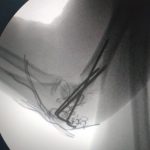

İlk kez bir Türk doktor tarafından gerçekleştirilen ve çocuk dirsek kırıklarının kapalı tedavisi için geliştirilen yeni bir ameliyat tekniği, Journal Of Klinical Medicine dergisinde yayımlandı.

Ortopedi ve Travmatoloji Uzmanı Dr. Mustafa Kınaş ve Uz. Dr. Ozan Turhal tarafından 46 hasta üzerinde başarılı bir şekilde uygulandıktan sonra makale haline getirilen teknik, tek hekim tarafından kolayca tatbik edilen ve başarılı sonuçlar alınan bir teknik olarak tıp literatüründeki yerini aldı.

Böyle bir ameliyatın tek hekimle yapılmasının çok zor olduğunun altını çizen Uz. Dr. Mustafa Kınaş, geliştirmiş olduğu bu teknikle kolayca başarılı sonuçların alınabildiğini söyledi. Yaptığı çalışma hakkında bilgi veren başarılı Mustafa Kınaş, “Çocuk dirsek kırıkları çok sık karşılaşılan kırık çeşitleridir. Genellikle ameliyat edilmesi gereken kırıklar olarak karşımıza çıkar. Bu kırıklar açık ve kapalı olarak ameliyat edilir. Tedavisi zor ve genellikle 2 ortopedi uzmanının beraber yardımlaşacak yaptığı bir ameliyat çeşididir. Biz zorunlu hizmette bu hastaları tek başımıza ameliyat ederken, arkadaşımız Uz. Dr. Ozan Turhal benim ameliyatımı gördü. Tek başıma yapmış olmama şaşırdı ve bu tekniğin dünya kütüphanesine eklenmesi gerektiği fikrini ortaya attı. Süreç bundan sonra başladı. Yaklaşık 46 hasta üzerinde çalışma yaptık. Hastaları tedavi ettik ve takibini yaptık. Tedavi ve sonuçlarını yazarak makalemizi dergiye gönderdik. Bu tekniğin literatürde ilk olması sebebiyle çok çabuk bir şekilde kabul edildi ve yayınlandı” dedi.